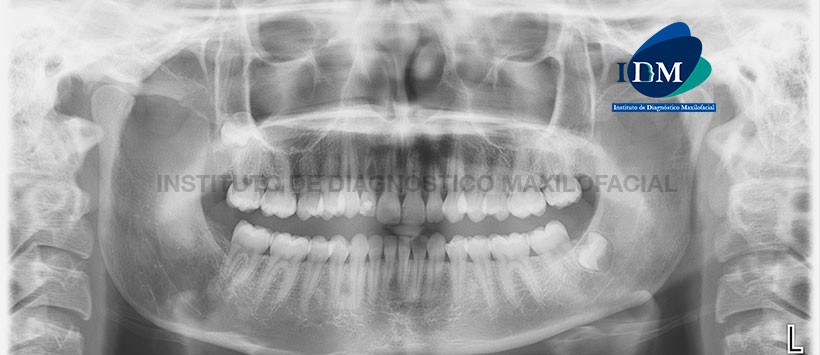

A la evaluación de la radiografía panorámica (Figura 1) se aprecia una imagen radiolúcida a nivel del tercio medio radicular de la pieza 1.2. Por otro lado se aprecia la pieza 1.8 retenida y la no visualización de los gérmenes dentarios para las piezas 2.8 y 4.8.